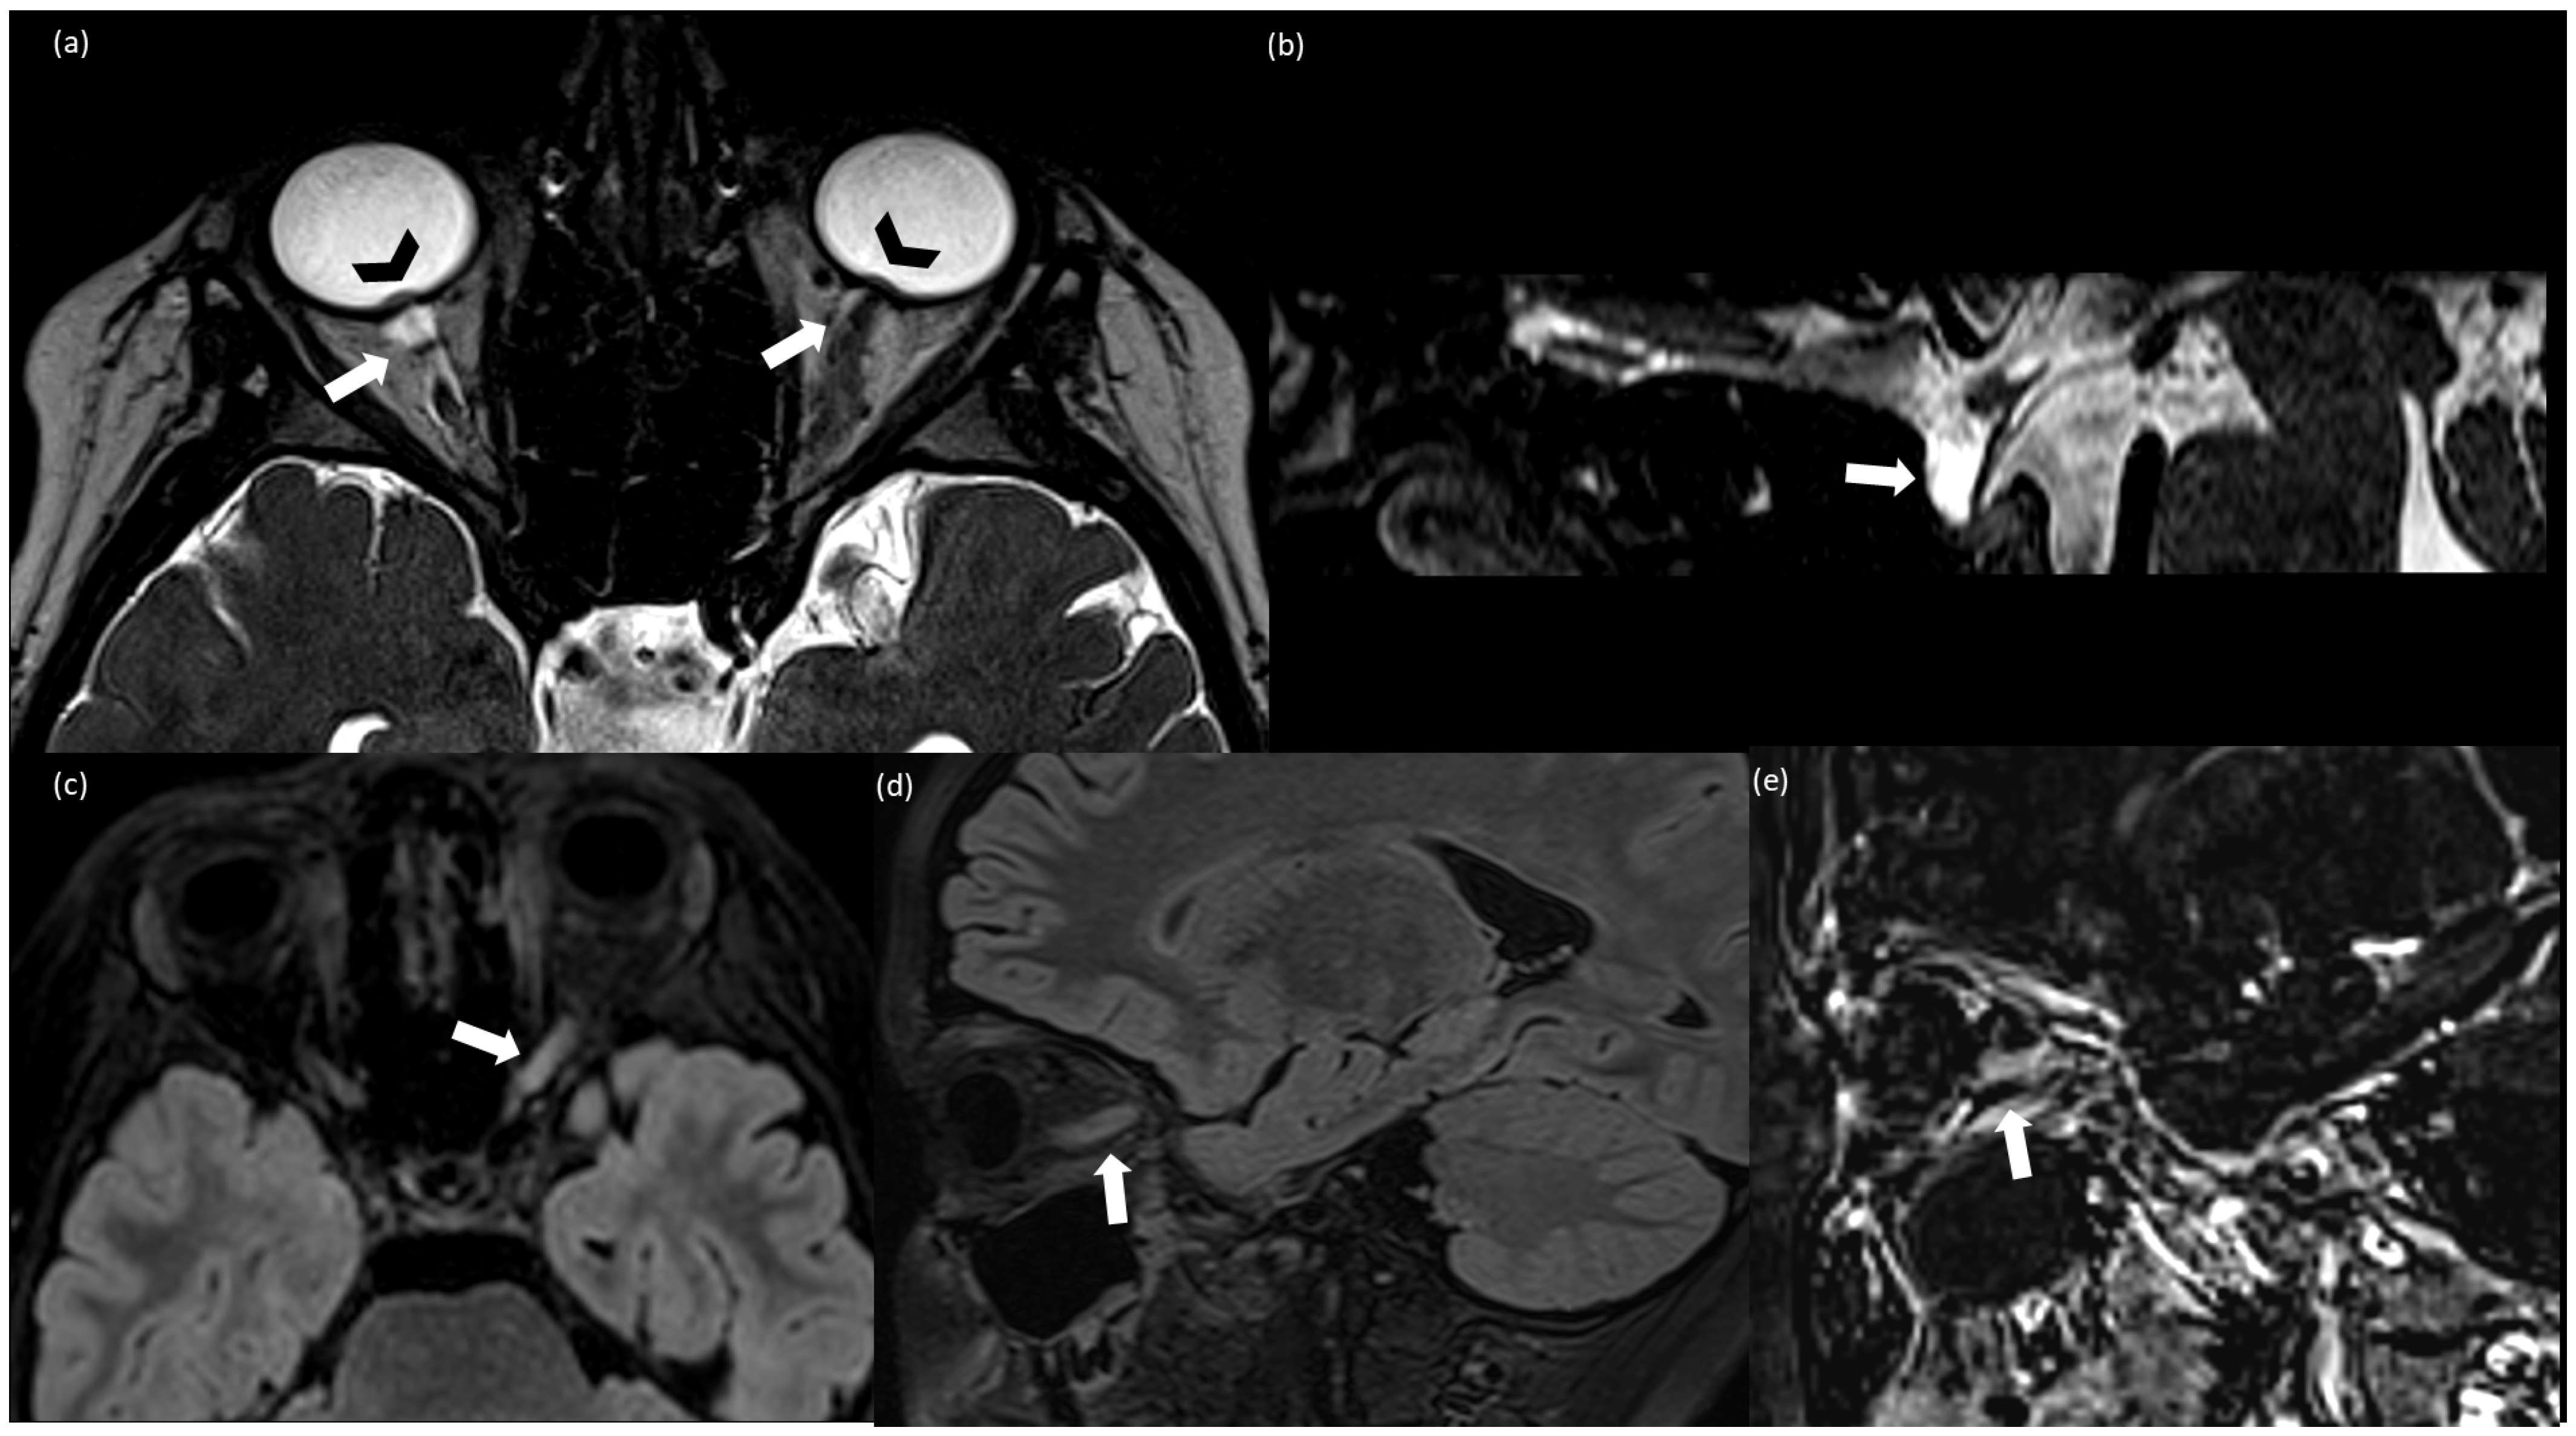

2. Case Report

| 5/ Alqahtani et al., 2023 [7] | 12/M | 28.8 | 35 | Normal | 75 (89% L, 4% N, 3% M, 1% E) | No | flattening of the posterior globes, prominent both Meckel cave, optic nerves tortuosity | Headache Bilateral reduced visual acuity | asymmetric bilateral papilledema and abnormal visual acuity and visual field. | Acetazolamide, methylprednisolone 30 mg/kg/day was administered for 5 days followed by low doses acetazolamide 10 mg/kg/day (duration treatment 3 months) |

| 6/ Valdrighi et al., 2021 [8] | 12/M | BMI not specified Obese | 52 | Normal | 157 (68% L, 11% N, 17% M, 4% E) | No | a partially empty sella, intraocular protrusion of the optic nerves, flattening of the posterior globes, narrowing of the venous sinuses, and tortuous optic nerves multifocal leptomeningeal enhancement. After 4 months from the onset: T2 hyperintense cerebellar and pontis lesions | Blurred vision, nausea, vomiting, headaches, cranial nerve VI palsies. | Bilateral papilledema Normal visual acuity and visual field. | Acetazolamide, methylprednisolone. After radiological relapse: monthly IV immunoglobulin |